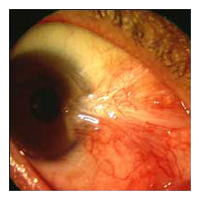

Before Pterygium Removal  After

Pterygium Removal

Technique for No-stitch Pterygium Surgery

In no-stitch surgery, the patient is lightly sedated to ensure

comfort, and the eye is completely numbed, so there is no way to see

the surgery occurring and no sensation of discomfort. The abnormal

tissue is removed and replaced with a thin autograft or amniotic

membrane. Over the next 2-4 weeks, the eye gradually returns to a

normal appearance.